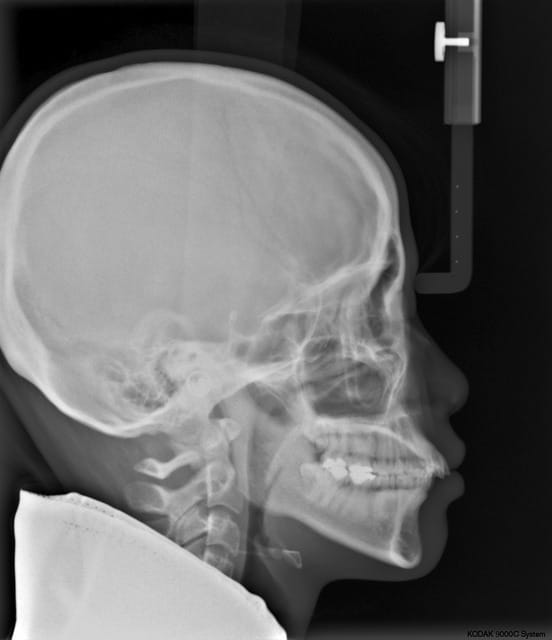

Patiente reçut en début d'année.

L'examen des éléments clinique montre qu'elle était border line extraction.

Vue que le profile et l’esthétique était correct, les enseignant on décider de commencer dans une optique de non extraction et de réévaluer a la fin de l'étape d'alignement.

Le traitement se déroule normalement.